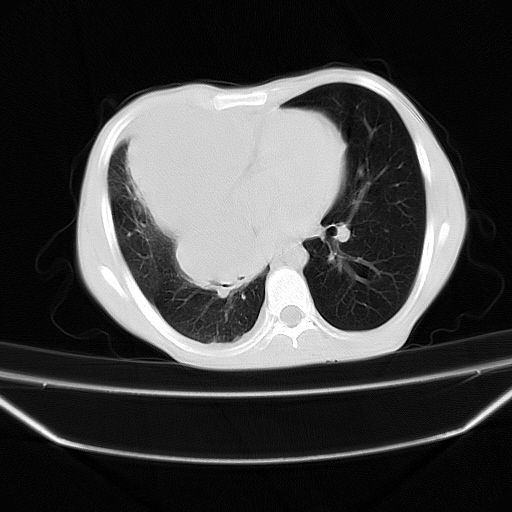

以下是引用zjzjr在2008-7-20 12:57:00的发言:[br]考虑为生殖源性肿瘤(内胚窦瘤),侵袭性胸腺瘤可能性大;右侧少量胸腔积液。

以下是引用xinliheng001在2008-7-20 21:17:00的发言:[br]右纵隔巨大分叶状软组织均质密度肿块,右上肺叶受压明显,纵隔右移、胸膜受累有少量积液和结节样增厚。应增强扫描一定会有更具诊断价值的信息。

以下是引用xinliheng001在2008-7-20 21:17:00的发言:[br]右纵隔巨大分叶状软组织均质密度肿块,右上肺叶受压明显,纵隔右移、胸膜受累有少量积液和结节样增厚。应增强扫描一定会有更具诊断价值的信息。